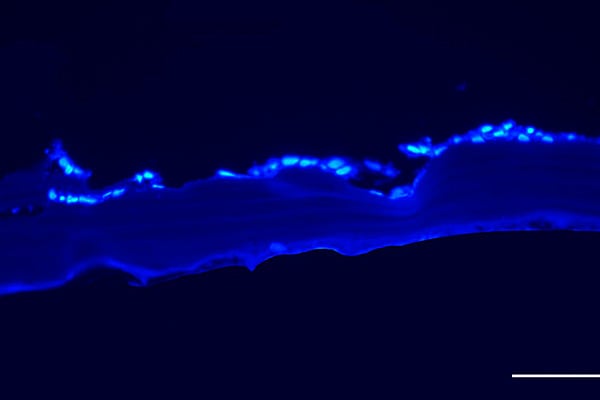

Experimento in vitro para comprobar que las células corneales "podían procesar la escama de los peces".

Mientras, explica que esta investigación se ha desarrollado en dos fases principales. La primera consistió en experimentos in vitro para comprobar que "las células corneales podían procesar la escama de los peces" y que luego permitiera "la implantación corneal en pocillos de laboratorio como medio de cultivo y evaluar que esas células corneales proliferaban y elaboraban estructuras similares".